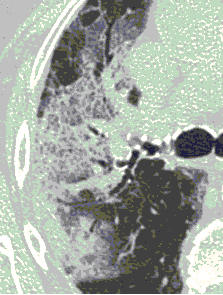

4.3. ЛУЧЕВАЯ ДИАГНОСТИКА COVID-19

Методы лучевой диагностики применяют для выявления COVID-19 пневмоний, их осложнений, дифференциальной диагностики с другими заболеваниями легких, а также для определения степени выраженности и динамики изменений, оценки эффективности проводимой терапии.

Стандартная РГ имеет низкую чувствительность в выявлении начальных изменений в первые дни заболевания и не может применяться для ранней диагностики. Информативность РГ повышается с увеличением длительности течения пневмонии. Рентгенография с использованием передвижных (палатных) аппаратов является основным методом лучевой диагностики патологии ОГК в ОРИТ. Применение передвижного (палатного) аппарата оправдано и для проведения обычных РГ исследований в рентгеновском кабинете. В стационарных условиях относительным преимуществом РГ в сравнении с КТ являются большая пропускная способность. Метод позволяет уверенно выявлять тяжелые формы пневмоний и отек легких различной природы, которые требуют госпитализации, в том числе направления в ОРИТ.

КТ имеет высокую чувствительность в выявлении изменений в легких, характерных для COVID-19. Применение КТ целесообразно для первичной оценки состояния ОГК у пациентов с тяжелыми прогрессирующими формами заболевания, а также для дифференциальной диагностики выявленных изменений и оценки динамики процесса. КТ позволяет выявить характерные изменения в легких у пациентов с COVID-19 еще до появления положительных лабораторных тестов на инфекцию с помощью МАНК. В то же время, КТ выявляет изменения легких у значительного числа пациентов с бессимптомной и легкой формами заболевания, которым не требуется госпитализация. Результаты КТ в этих случаях не влияют на тактику лечения и прогноз заболевания при наличии лабораторного подтверждения COVID-19. Поэтому массовое применение КТ для скрининга асимптомных и легких форм болезни не рекомендуется. При первичном обращении пациента с подозрением на COVID-19 рекомендуется назначать КТ только при наличии клинических и инструментальных признаков дыхательной недостаточности (SpO2 < 95%, ЧДД > 22).

4. Все выявляемые при лучевых исследованиях признаки, включая КТ-симптомы, не являются специфичными для какого-либо вида инфекции и не позволяют установить этиологический диагноз. Вне клинической (эпидемической) ситуации они не позволяют отнести выявленные изменения к пневмонии COVID-19 и дифференцировать их с другими пневмониями и невоспалительными заболеваниями. Данные лучевого исследования не заменяют результаты обследования на РНК SARS-CoV-2. Отсутствие изменений при КТ не исключает наличие COVID-19 и возможность развития пневмонии после проведения исследования.